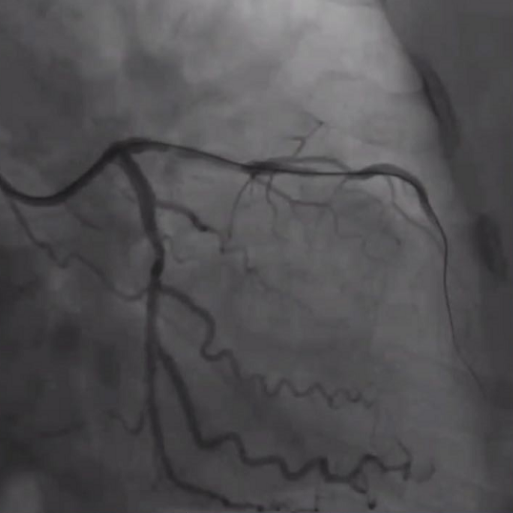

RCA CTO病变

RCA支架植入后